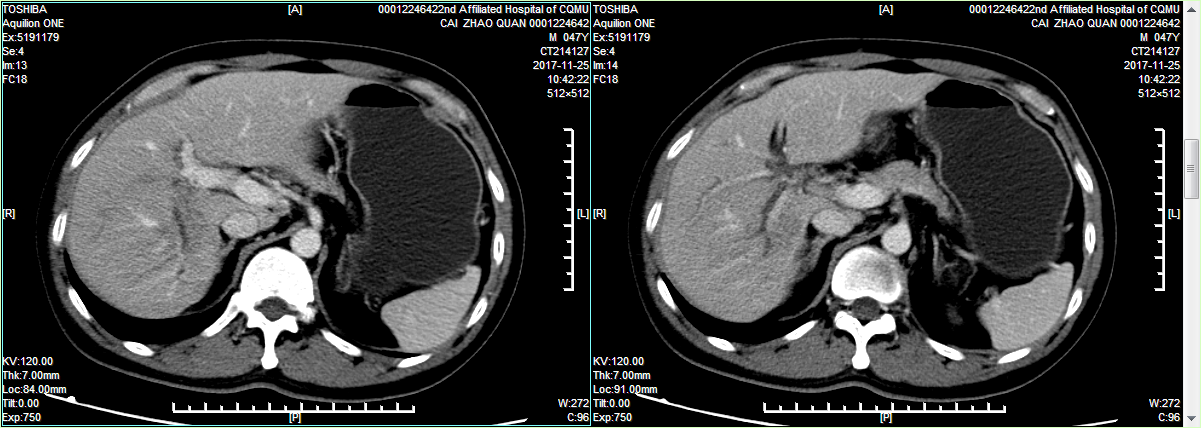

患者某,男,47岁,因胆道术后8+月,反复发热6+月,加重3天入院。患者8+月前在院外行了胆囊手术,术后患者出现腹痛、发热,考虑胆汁性腹膜炎,转入重庆其它医院予以穿刺引流、胆道支架置入等治疗,患者发热症状仍无好转,后慕名来我科治疗。在我科完善相关检查后,考虑诊断:1.右肝多发脓肿;2.右肝管狭窄?3.胆道术后。该患者病情复杂,在院外经长时间治疗后仍有反复发热症状,严重影响患者生活。因此,龚建平主任及刘作金副主任组织全科医生对该患者进行会诊,经我科专家共同探讨,一致认为该患者需要采取积极手术治疗,手术方式要考虑行右半肝切除术,但针对该患者的具体手术方式,专家组们提出了以下问题:1.该患者为青壮年男性,为良性病变,如采取传统的开腹右半肝切除,手术切口大(约30cm),且将切断腹壁肌肉及神经,势必对患者日后的生活和工作带来巨大的影响;2.如采取腹腔镜右半肝切除,将避免以上并发症。但该患者既往有腹腔手术史,有术后腹腔感染,肝脏长期反复感染、形成脓肿,腹腔内粘连致密;其次,患者CT和MRCP均提示右侧胆管、血管均有解剖变异,既往有右侧胆道损伤,若采取腹腔镜手术,难度极大。患者腹腔镜粘连重,术中可能损伤胃、十二指肠、结肠、膈肌等重要脏器;患者肝门结构解剖不清、合并肝脏脓肿,切肝时可能导致难以控制的大出血,从而危及生命,这对主刀医生来说,是一个巨大的挑战。如果选择行开腹手术,医生操作的难度和风险将大大降低,但患者将承受永久的创伤;如果选择行微创手术,将增加医生的手术难度和风险,但患者的创伤将会大大减少。最终,本着让患者受益的原则,龚建平主任和刘作金教授均决定为患者施行腹腔镜右半肝切除术,并得到患者的认可。

术前刘作金教授团队利用目前先进的“精准肝切除”理念,对患者的病情进行全面评估,仔细阅读患者的影像资料,进行手术规划,制定手术方案。目的在于彻底清除病灶的同时,确保剩余肝脏结构的完整和功能性体积最大化,并最大限度控制手术出血和全身性创伤侵袭,最终使手术患者获得最佳康复效果。

该患者变异的右侧肝蒂